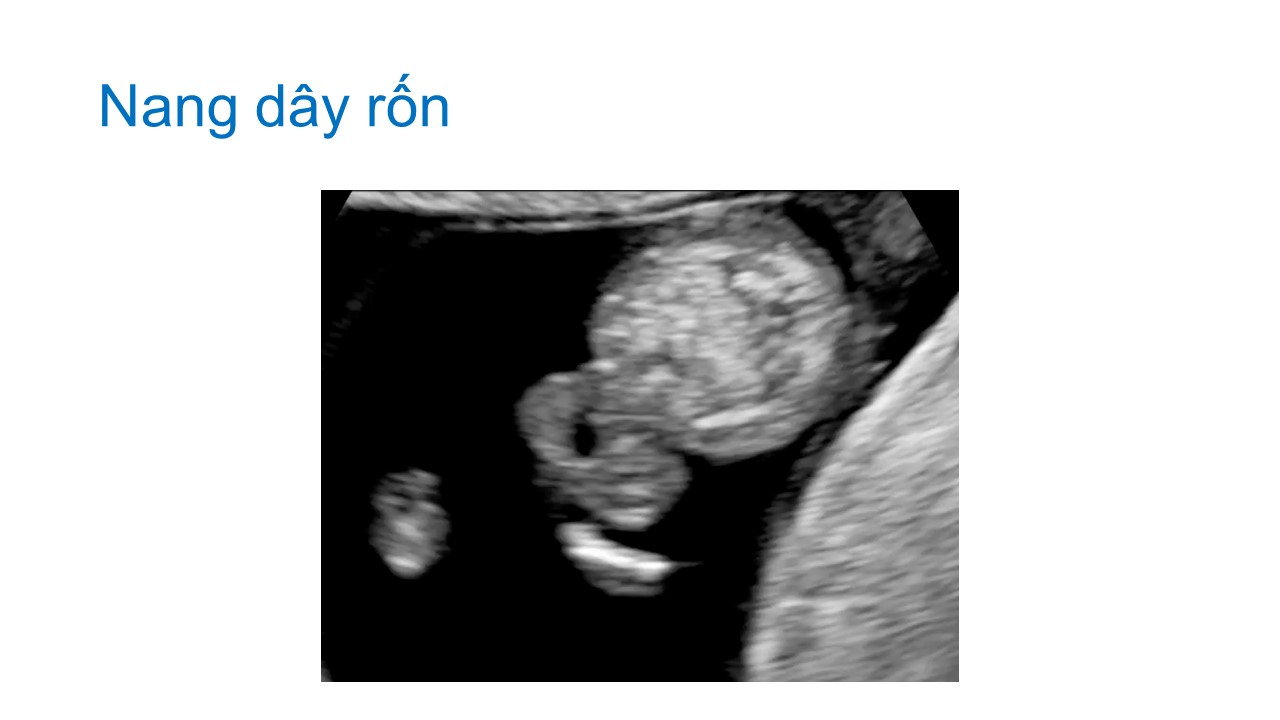

Siêu âm hình thai học quý I